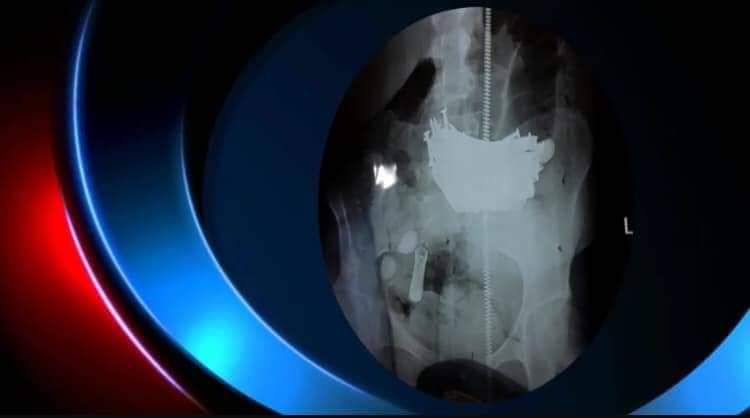

العراق - الكوثر: تمكن فريق طبي في المثنى بإشراف الجراح علي فائق صادق من استخراج "مسامير حديدية" بوزن كيلو غرام من معدة مريضة "18" عاماً تعاني من مرض نفسي.

وبحسب بيان لمستشفى الحسين التعليمي في المثنى،  فان المريضة كانت تعاني من آلم حاد في البطن منذ أكثر من شهر وبعد اجراء الفحوصات السريرية والاشعة اتضح وجود نزيف بالمعدة نتيجة تمزق جدار المعدة جراء تناولها لكميات من {المسامير الحديدية}.

واضاف البيان، ان المريضة خضعت لمراقبة طبية لمدة عشرة ايام بعد اجراء العملية التي استمرت لساعة ونصف قبل ان تتماثل للشفاء التام.